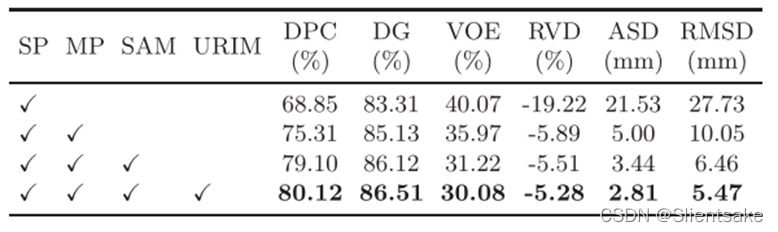

消融实验:

为了验证方法中每个组件的有效性,从单相(PV相)ResNeXt-50网络开始,逐步添加模块。表3总结了定量结果,其中SP表示单相分割,MP表示多相分割,只需在四个卷积块处添加PV和ART特征(将此融合策略表示为FLF)。可以看出,添加多阶段信息可使DPC的性能提高+6.46%;在DPC中,采用SAM模块融合功能将性能提高+3.79%;通过URIM模块细化不确定区域,可在DPC中获得+1.02%的性能增益。

表3:消融实验的定量结果